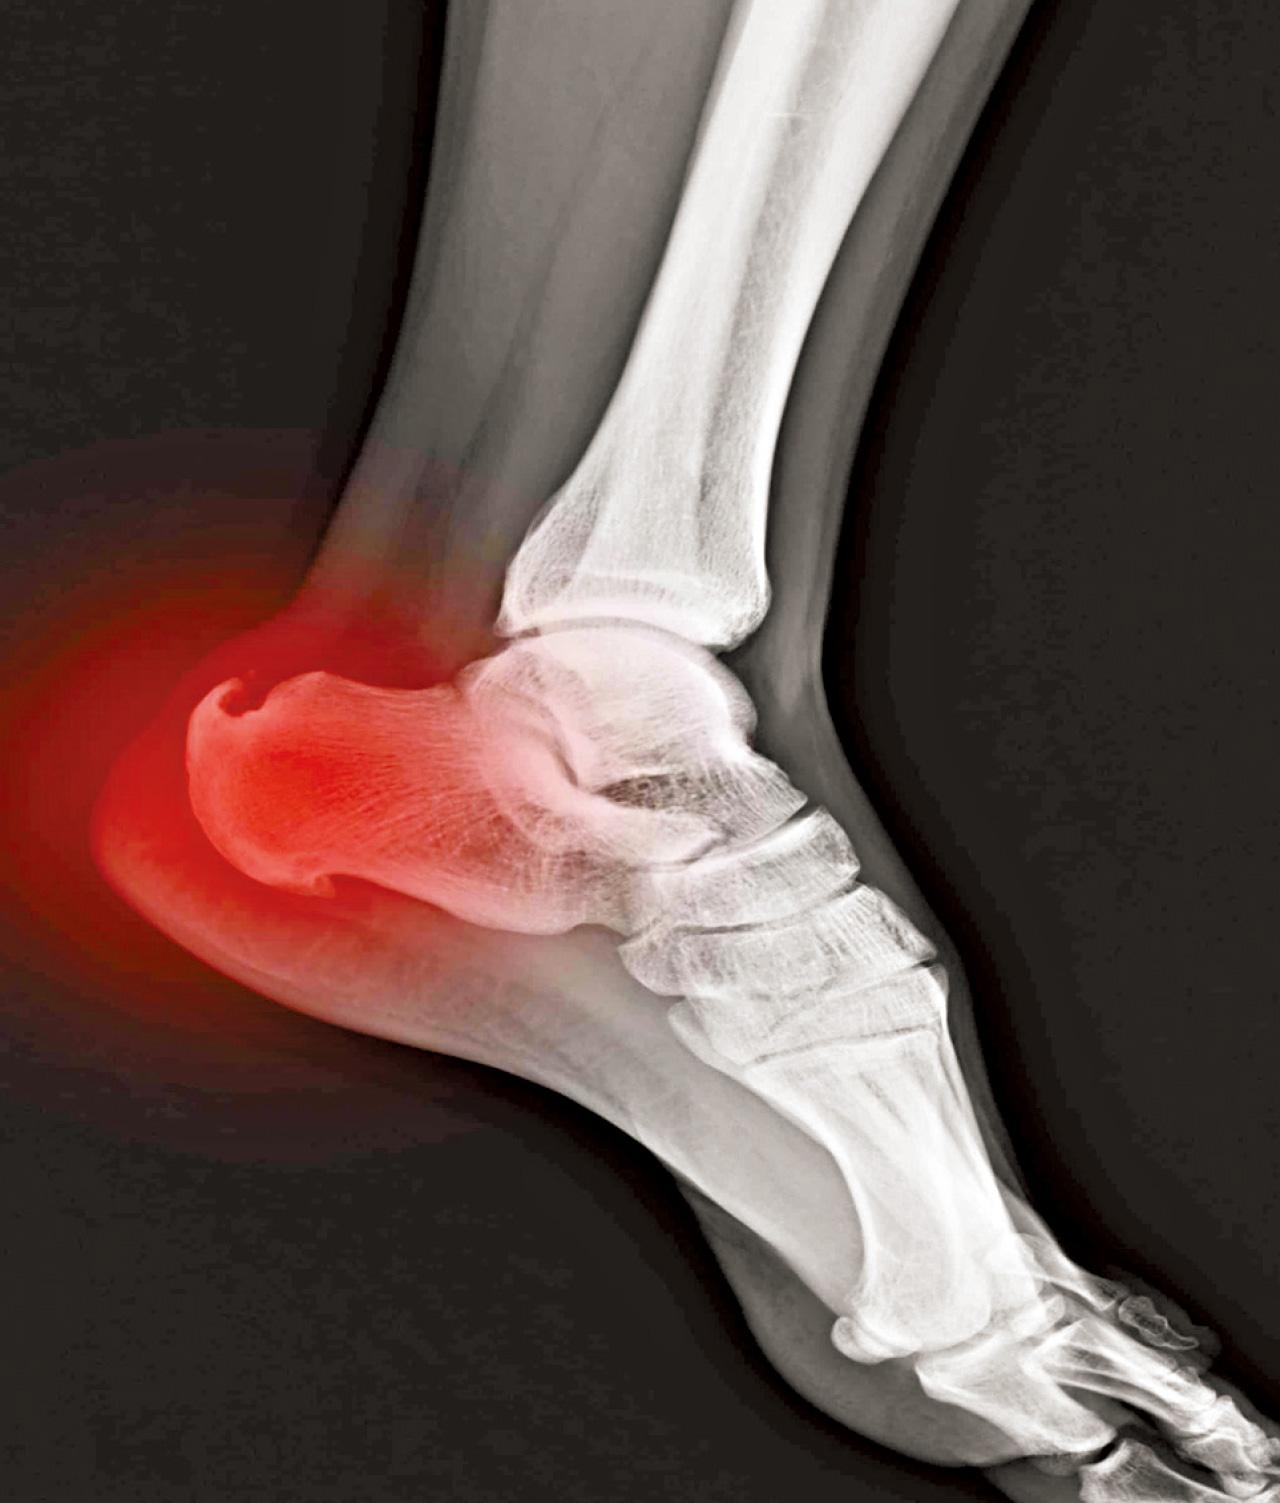

骨刺會導致痛症?

骨刺

骨刺一般情況不會引起疼痛,大部分情況下,導致長期痛症的原因包括姿勢問題、運動發力錯誤、勞損等,而在關節炎情況比較嚴重時,可能會導致關節面摩擦增多而導致疼痛和活動受限。

為甚麼會有骨刺呢?其實透過觸摸一下雙腳腳眼可略知一二,身體上一些較突出的位置都是由肌肉或韌帶反覆拉扯而形成。而骨刺的形成一樣是因為軟組織經過反覆用力或肌肉繃緊而造成。所以,其實骨刺是伴隨著大量軟組織繃緊及勞損問題。

治療方面,透過物理治療運動及手法治療能增加強關節靈活性及力量,雖然過程中不會處理骨刺,但一樣可以減低痛症以及關節受限問題,所以真正要解決的是軟組織繃緊問題以及骨刺形成的成因。至於透過手術切除骨刺,這並不是一勞永逸的方法,有些個案在切除骨刺後痛症亦無法減少,一樣需要物理治療去根治痛症問題。

改善運動習慣、避免重複發力而缺乏休息、增加肌肉力量等均可減少身體代償,才是處理根本問題的正確之道。